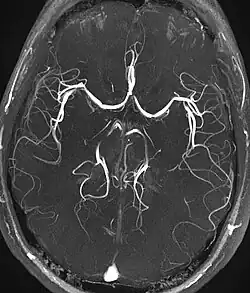

Magnetic resonance angiography (MRA) generates pictures of the arteries to evaluate them for stenosis (abnormal narrowing) or aneurysms (vessel wall dilatations, at risk of rupture). MRA is often used to evaluate the arteries of the neck and brain, the thoracic and abdominal aorta, the renal arteries, and the legs (called a "run-off"). A variety of techniques can be used to generate the pictures, such as administration of a paramagnetic contrast agent (gadolinium) or using a technique known as "flow-related enhancement" (e.g., 2D and 3D time-of-flight sequences), where most of the signal on an image is due to blood that recently moved into that plane (see also FLASH MRI).[53]

Techniques involving phase accumulation (known as phase contrast angiography) can also be used to generate flow velocity maps easily and accurately. Magnetic resonance venography (MRV) is a similar procedure that is used to image veins. In this method, the tissue is now excited inferiorly, while the signal is gathered in the plane immediately superior to the excitation plane—thus imaging the venous blood that recently moved from the excited plane.[54]